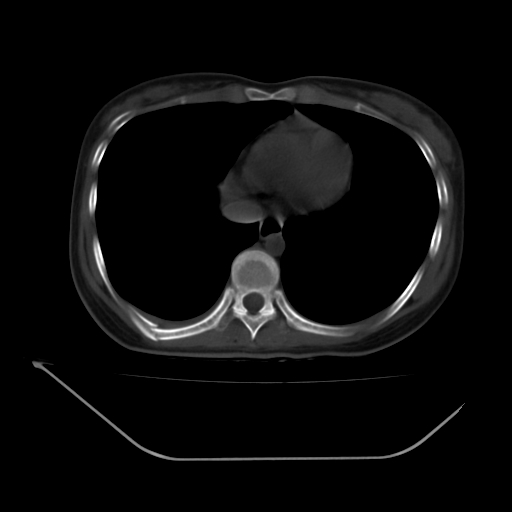

以下是引用liuyue在2008-7-19 13:02:00的发言:[br]1.肝右叶后下段及右肾挫裂伤伴腹腔积血。[br]2.右侧多发性肋骨骨折、横突骨折、右髂骨骨折伴周围软组织挫伤。[br]3.右侧腰大肌肿胀,并可见低密度影,如为气体,则肠道挫裂伤待除外。

以下是引用zhengfaming在2008-7-19 14:42:00的发言:[br]1.肝右叶后下段及右肾挫裂伤伴腹腔积血。脾脏挫裂伤待排[br]2.右侧多发性肋骨骨折、横突骨折、右髂骨骨折伴周围软组织挫伤。[br]3.右侧腰大肌肿胀,并可见低密度影,如为气体,则肠道挫裂伤待除外